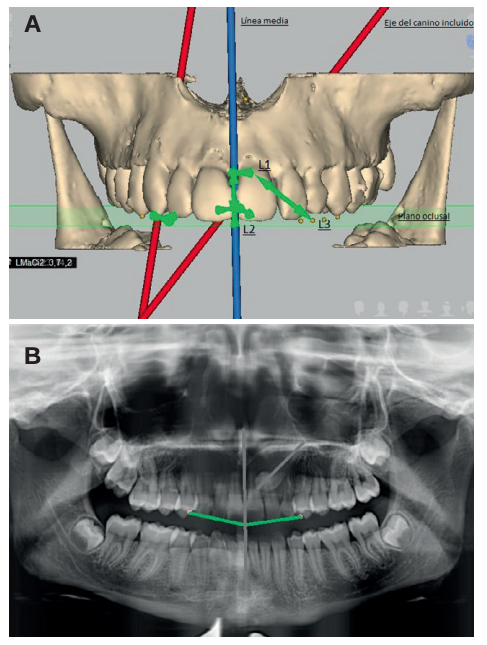

Methods: An orthodontic study of the maxilla using orthopantomography with cone beam computed tomography (CBCT) at the Madrid European University Clinic was performed on 27 patients selected with 36 maxillary impacted canines. Three reference lines were drawn based on the distance from the cusp of the canine to the occlusal plane (L1), to the midline (L2) and to its ideal eruption site (L3), in both the orthopanthomography and the CBCT. As ideal reference values, we selected a control group of 36 erupted maxillary canines.